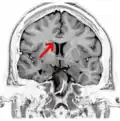

Sagittal section of a brain, front part to the left. The corpus callosum can be seen in the center, in light gray